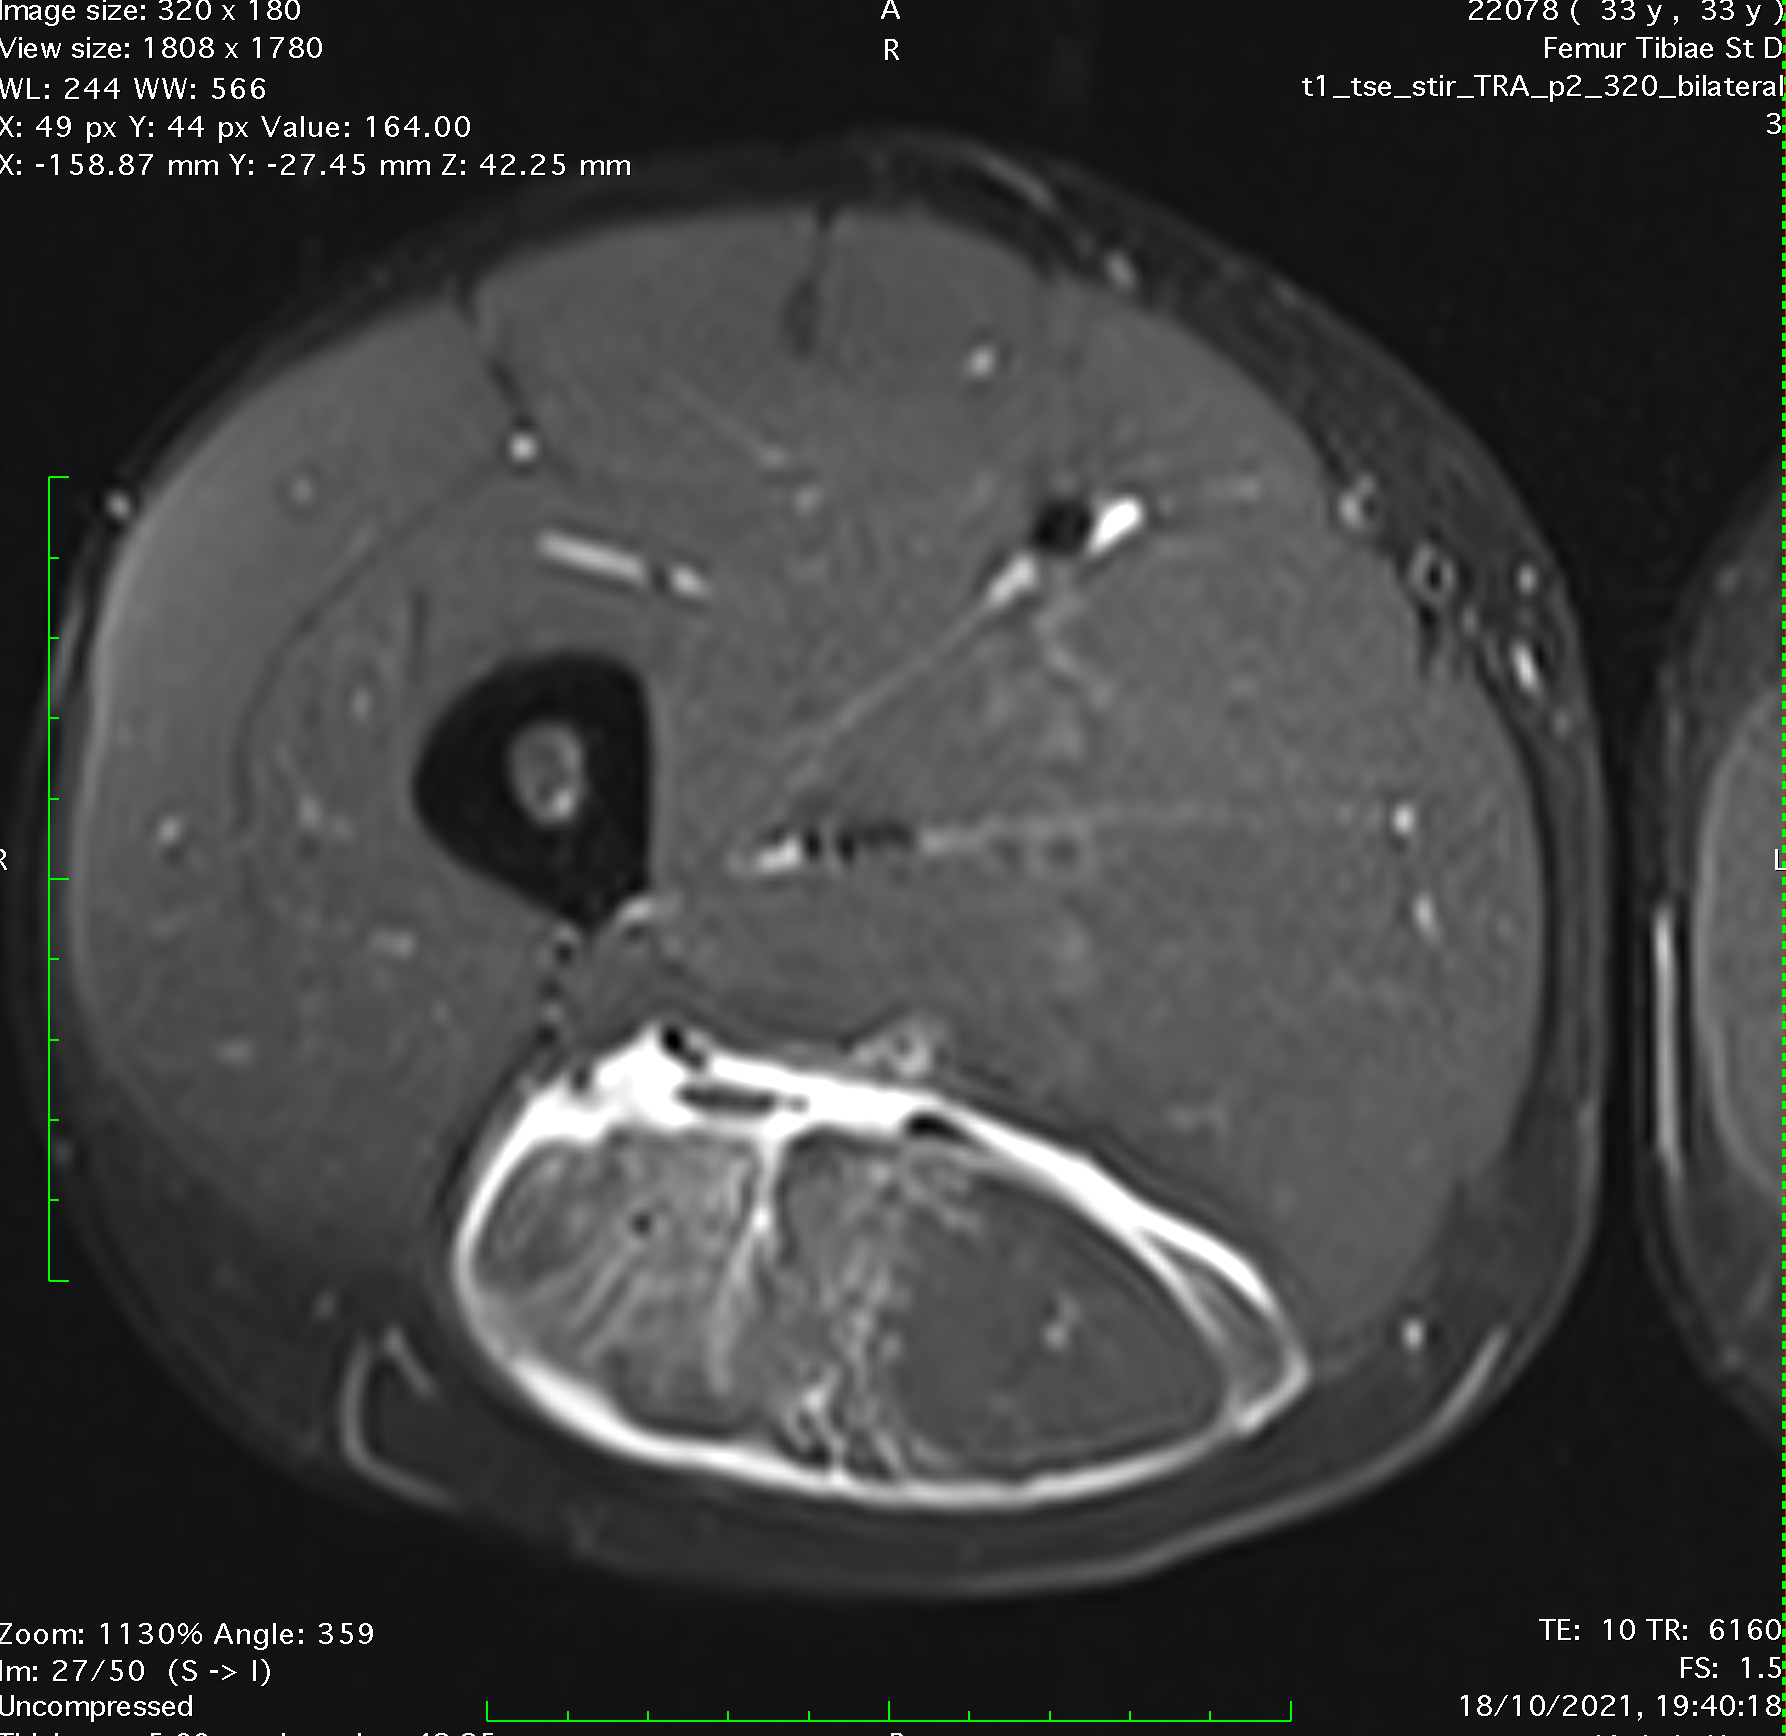

One full week local ultrasound guided injection therapies were administered in daily sessions. Patient was advised to take lot of amino acids (as they are more easily absorbed and used than proteins) and vitamins. After almost two weeks we decided to make a control MRI. My main concern was the rate of regeneration of the ruptured tendon. Ultrasound showed excellent progress but I needed to be sure by doing a control MRI. A mistake in assesment or progressing with rehabilitation to quickly could mean a new reinjury and much more complicated situation.

MRI of hamstring intramuscular biceps tendon injury two weeks into the rehabilitation

MRI confirmed a great progress and intramuscular tendon healing! Comparing the two MRIs muscle healed as well and there was no fluid around the muscle.

Comparation of MRIs, left one few days after the injury, right one after first cycle of therapies, two weeks later.